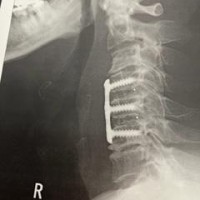

龍香店主のレントゲン!

レントゲンで見えるチタンのプレートです。

ビスが6本で固定してあります。これで

4.5.6番目の頚椎を一つに固めてしまうらしい。

間に人工の椎間板が二枚入っているらしい…

レントゲンでは見えませんが…